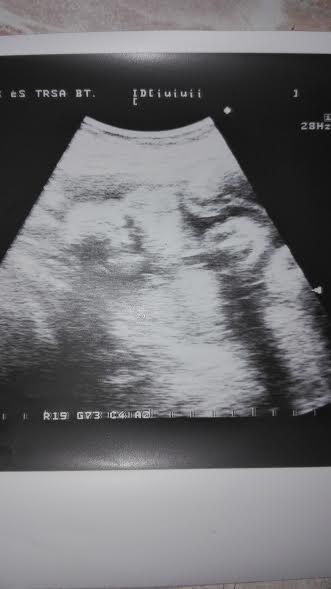

Babácskával is jól alakulnak a dolgok, már 1100 g környékén van a súlya, nagyon jól érzi bent magát. Bár még legyen is bent jó sokáig, hiszen még csak a 29.hetet töltjük. Próbálok már összehozni egy pocakos képet is nektek, de vagy "fotós" hiányban szenvedek, vagy pedig én nem érzem magam fotogénnek. Leginkább mostanában kövérnek érzem magam. És hiába tudom, hogy nem híztam még sokat, és hiába mondja orvos, védőnő, hogy ne aggódjak, én magamhoz képest most tényleg kövér vagyok. Legalább 2 kilóval vagyok nehezebb, mint mikor Lucát szültem. És ezt érzem. Nehezebb a mozgás, hamarabb kifulladok, és néhány hajszálér is megjelent a lábamon. Jó persze, ez nem tragédia, csak saját magammal szemben vannak ilyen elvárásaim, aminek nem tudok most megfelelni.